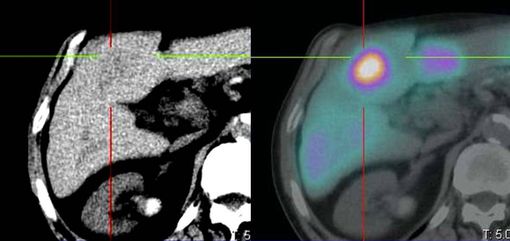

«Tecnicamente - spiega il Dott. Diego De Palma, Direttore della Medicina nucleare - dapprima si procede con uno studio diagnostico mediante un radiofarmaco che, iniettato, permette di evidenziare la dislocazione e la diffusione delle lesioni epatiche, così da valutare la fattibilità del trattamento e stabilire, insieme all’esperto di Radioprotezione della Fisica sanitaria, la corretta attività terapeutica. Successivamente, a distanza di 3-4 settimane, si procede con la somministrazione della terapia, cioè con l'iniezione delle microsfere radioattive».

L'operazione è delicata e si svolge nelle sale di Radiologia interventistica: a seconda della collocazione delle lesioni, il radiologo raggiunge con un catetere l'arteria epatica nel punto più idoneo per colpire in modo mirato. Una volta aperta la strada, è il medico nucleare che somministra le microsfere che, a migliaia, si vanno a posizionare nei vasi capillari che irrorano le lesioni tumorali da distruggere con le radiazioni.

Le microsfere hanno infatti un diametro tale da permettere di raggiungere i vasi capillari, ma non di andare oltre: si evita così il rischio che ritornino nei grandi vasi venosi che le porterebbero nelle altre parti dell'organismo causando pericolose ulcere. «È proprio per questo motivo - aggiunge De Palma - che lo studio con il radiofarmaco che precede il trattamento richiede grande attenzione: alcuni tumori epatici, infatti, derivano da malattie cirrotiche che potrebbero aver alterato la circolazione intorno al fegato mettendo a rischio il paziente durante il trattamento vero e proprio».